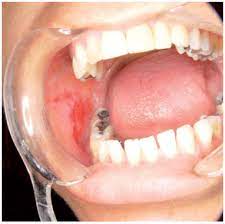

Specially formulated homeopathy treatment for lichen planus at Welling Clinics usually clears within a few months. Borax is another common homeopathic medicine used for treating oral lichen planus. It offers excellent treatment which has a success rate of over 85 It offers immuno-correction hence gives deep-level healing. It offers long-lasting cure instead of temporary. Oral Lichen Planus lesions may be associated with patchy brown melanin pigment deposits in the oral mucosa. One should think of homeopathy when the case is recently detected and not tampered with steroids. The major benefits of homeopathy for Lichen Planus treatment could be summarized as under.

Here is one such case where patient was severely affected by the disease. Arsenic album - White patches with ulceration of mouth dryness and burning in mouth tongue dry clean and red metallic taste in mouth anxious and restless patient. Homeopathy is the first line of treatment for Lichen Planus.

Plantago is one of the best Homeopathic medicines for oral lichen planus. Merc Sol is a natural medicine for oral lichen planus and. Yeah Homeopathy can cure Lichen planus completely.